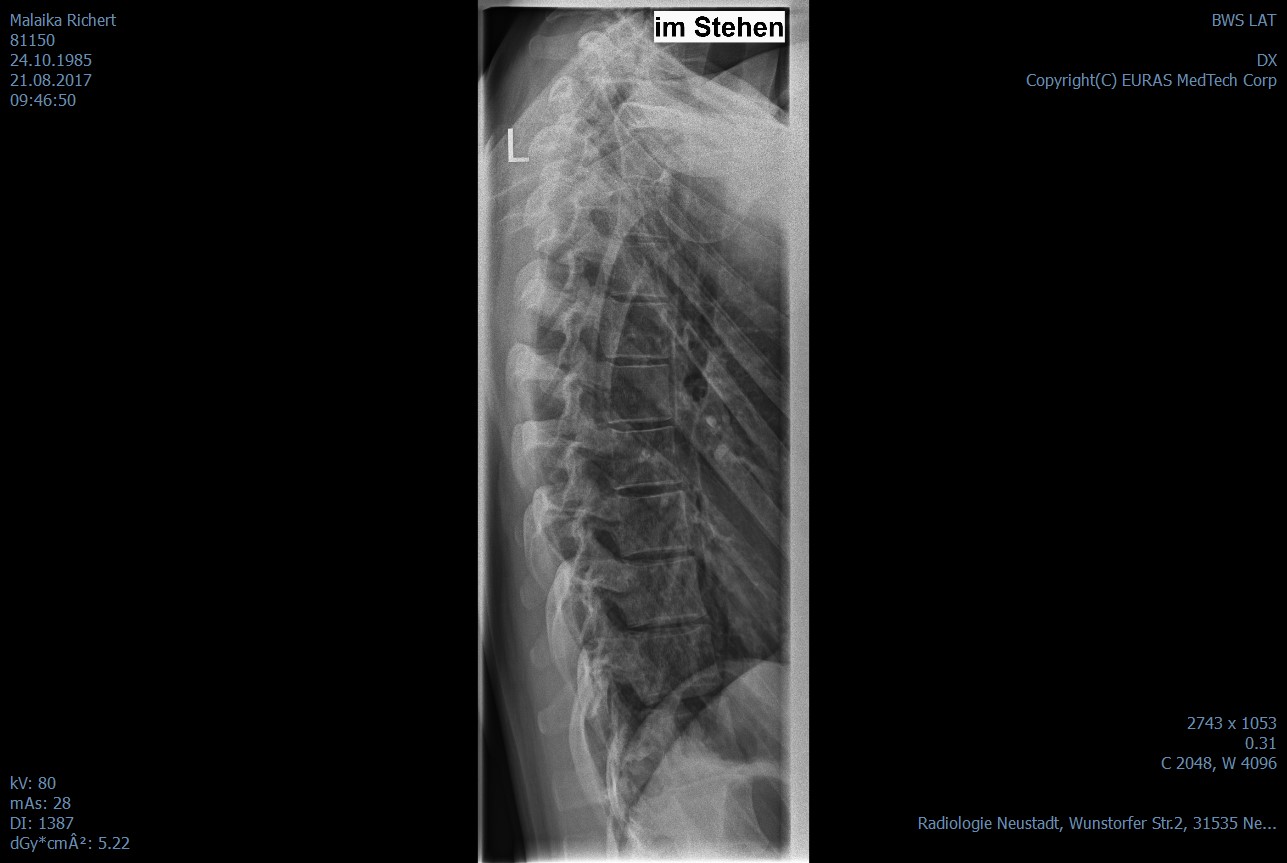

Ich hoffe ich habe alles erwähnt. Was soll ich tun? was meint und empfehlt ihr mir? Ich habe die Röntgenbilder mit eingefügt.

Unbenannt.jpg

(82.84 KiB) Noch nie heruntergeladen

Zuerstmal bin ich irritiert, weil ich nicht verstehe, wie ein Arzt bei der Wirbelsäule von einer Skoliose sprechen kann. Von einer Skoliose spricht man erst ab 20°, und das sind vielleicht gerade mal 5°, so wie ich das schätze. Ich bin, wie gesagt, kein Fachmann, und ich konnte nur eine der beiden Dateien öffnen, aber das scheint mir falscher Alarm zu sein. ;)